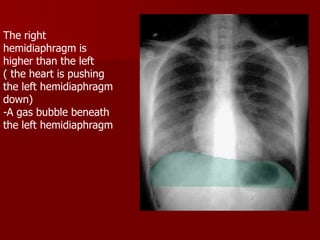

The right

hemidiaphragm is

higher than the left

( the heart is pushing

the left hemidiaphragm

down)

-A gas bubble beneath

RT

LT